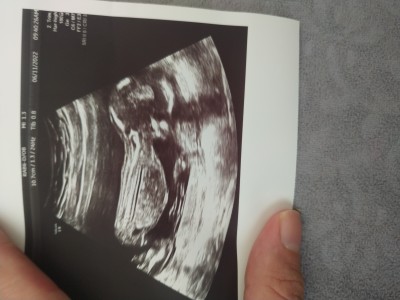

15+2 cinsiyet tahmininde bulunabilir misiniz

Gebelik haftası 15+2

Amin inşallah İlk bebeğimiz, doktor Kıza benziyor dedi ama Emin olamadı değişir mi bu haftadan sonra

Kiz  hayrli evlat olsun bacak arasindan gözüküyor

Erkek bebiş gibi Canım bacaklarının arasında eleman duruyor  :)

Kız bebek gibi geldi bana

Bacak arası boş canım %100 kız :)

14+5 de aynı görüntüyü yakaladı doktor bacak arasi bos ve kız dedi 18de yine kız dediler, 21+2 de ayrıntılı ultrason da erkek der bir başka doktor şok oldum ☺ ama cinsiyet yanılması çok oluyor 16.haftadan sonra genelde değişmez diyorlardi hala net değil benim için bi sonraki kontrolde net olur ☺

Bu hafta kontrole gittik kesin erkek dedi

Bu hafta gittik gösterdi pipisini kesin erkek dedi çok şaşırdık yine değişir mi bilmiyorum